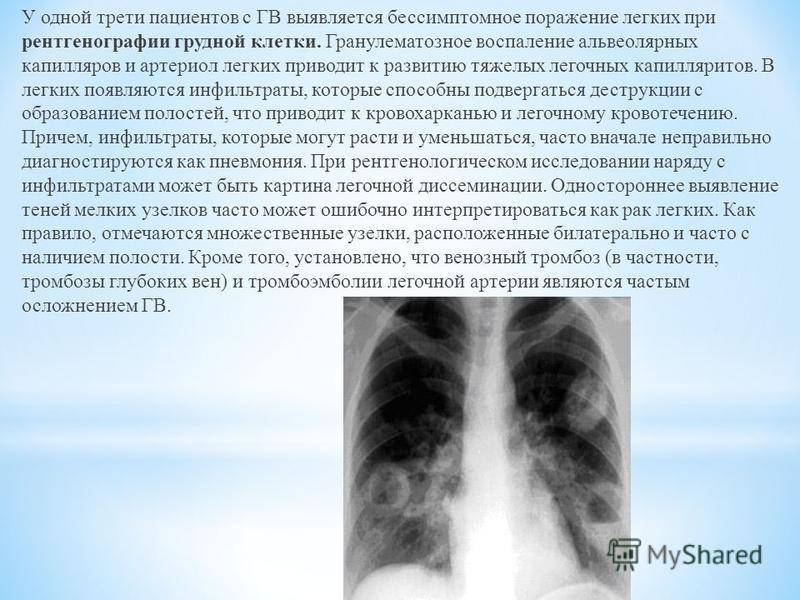

Медицинская тема: легочные осложнения при пневмонии